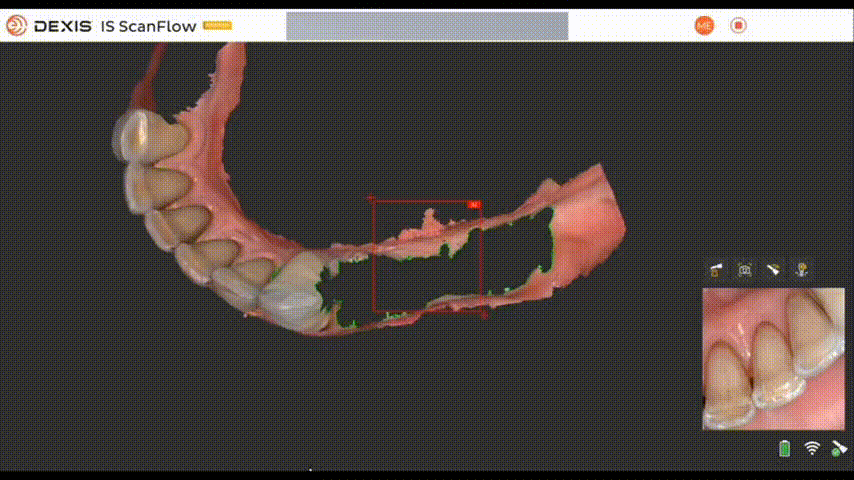

2. Демонтаж временных конструкций и сканирование анатомии профиля прорезывания

После снятия временных конструкций была проведена оценка состояния мягких тканей верхней и нижней челюсти.

При помощи встроенных функций в программе DEXIS IS ScanFlow производится вырезание временных конструкций и досканирование профиля прорезывания.

Нижняя челюсть